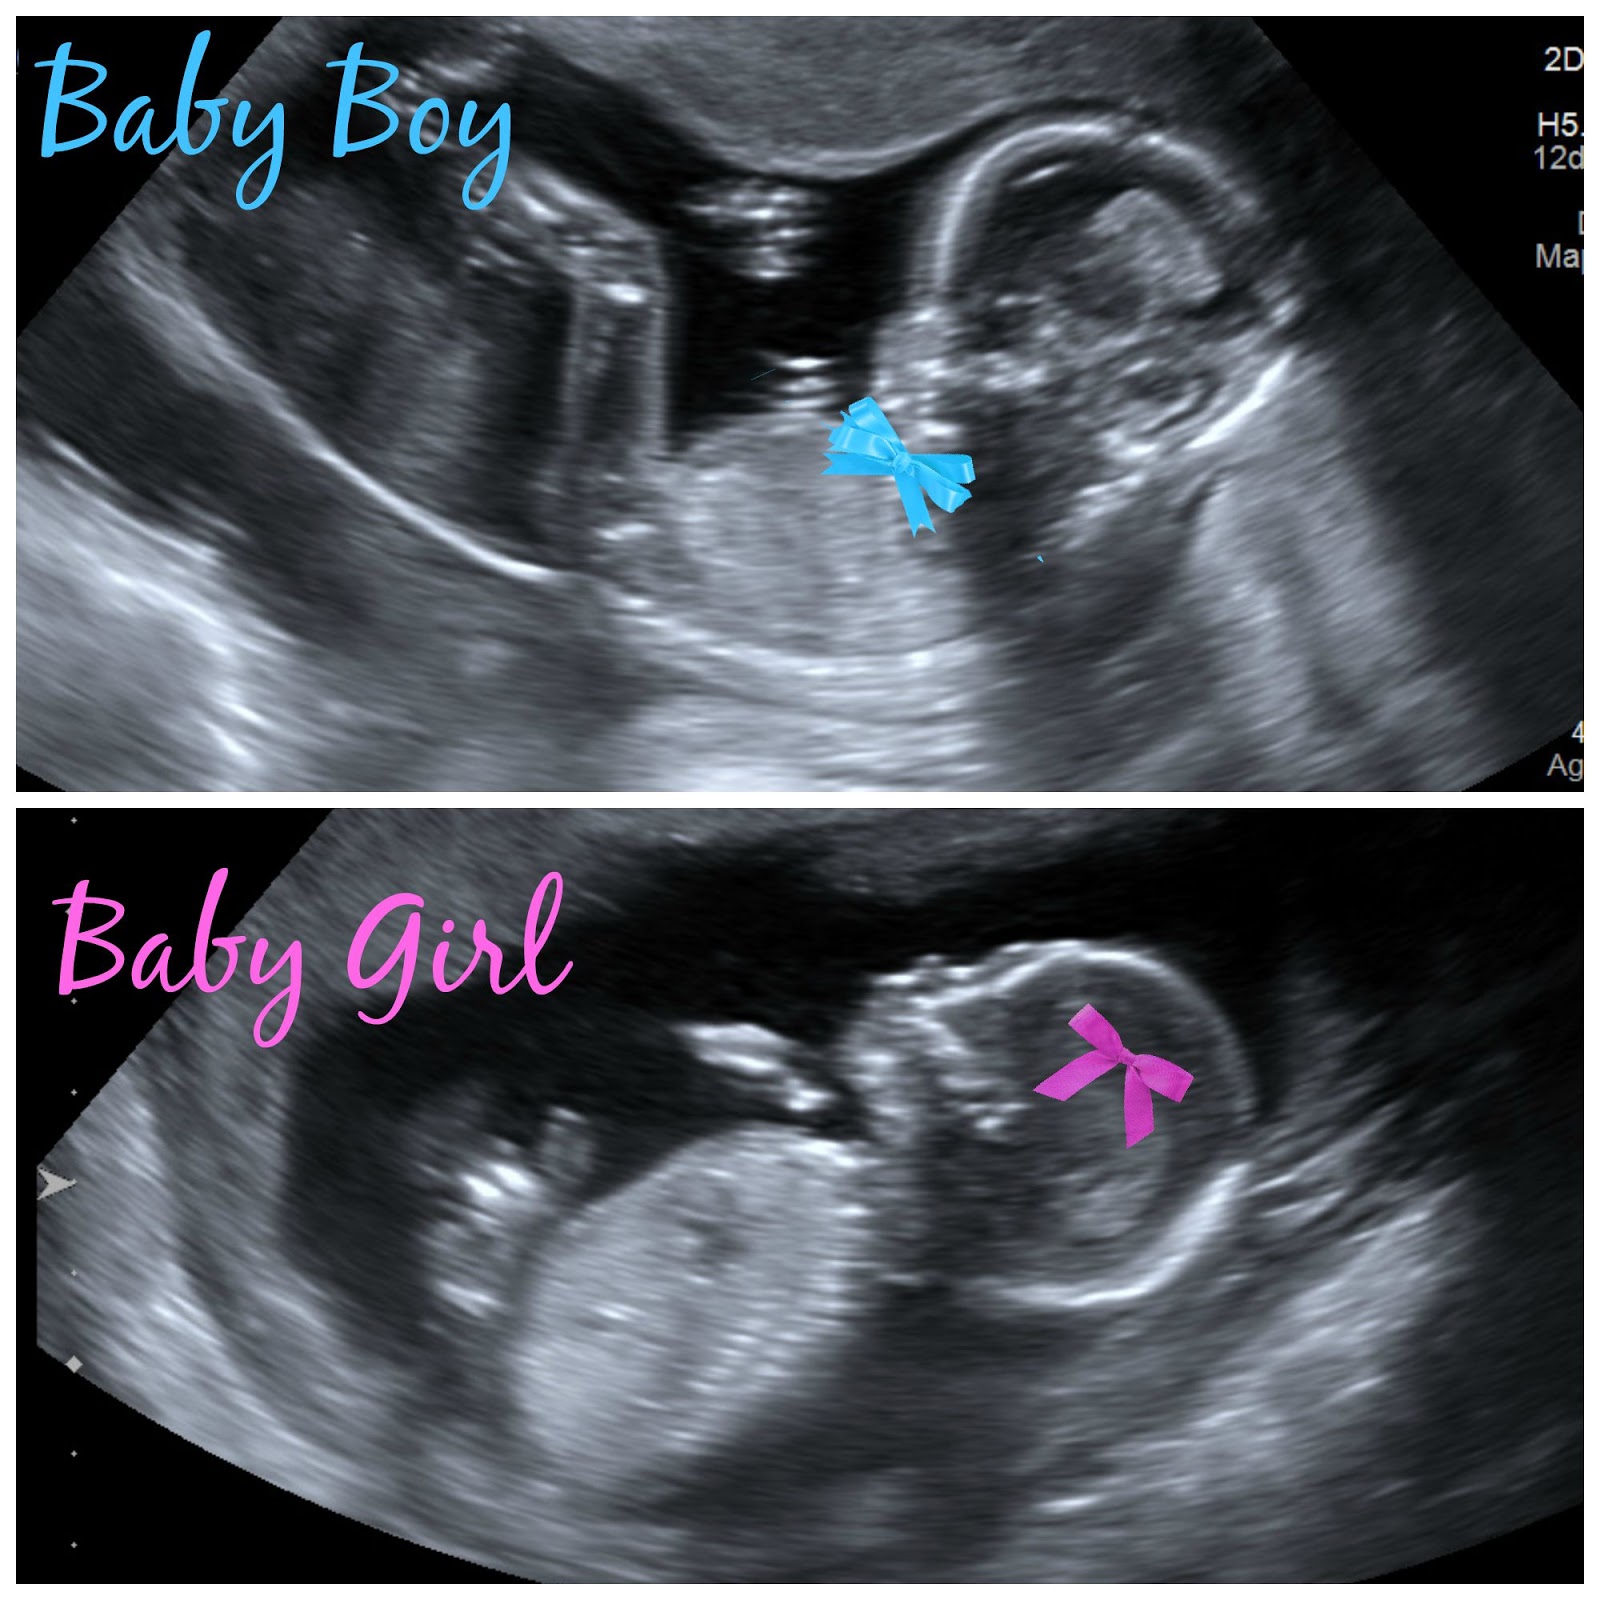

What We re Having Mark Robinson

Just Another Day 20 Weeks

Chels Hendrickson Boy Girl Twins 16 Week Bumpdate